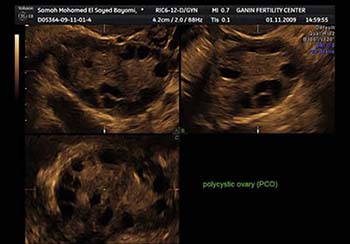

* تتيح هذه الأجهزة تقييم أفضل لحالات تكييس المبيض من حيث التشخيص وكذلك تقييم العلاج. فبالنسبة للتشخيص فإن هذه الأجهزة ومن خلال مسح المبيض تتيح دراسة المبيض في جميع قطاعاته وليس فقط من خلال منظر واحد له، بالإضافة أن أخر الأبحاث أفادت بأفضلية دراسة حجم المبيض كأحد علامات التشخيص.

* أما من حيث متابعة العلاج فذلك يتم من خلال تقييم حجم المبيض أيضا وهو ما يتيحه أجهزة ثلاثية الأبعاد ولا يتحيه الأجهزة العادية.